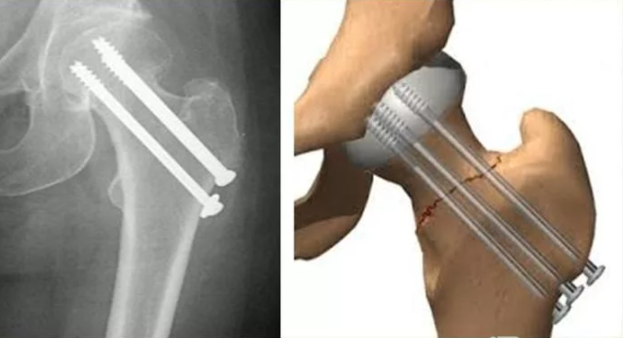

Чаще всего остеосинтез стержнями применим при переломе лучевой кости, шейки бедра, надколенника, ключицы, локтевого сустава. Очень важно, что остеосинтез стержнями в данном случае обеспечивает надежную фиксацию и правильное сращение. Есть показатели относительно характера. Так, остеосинтез стержнями может выступать необходимым элементом в том случае, если предъявляются жесткие требования по срокам реабилитации.

• наружный остеосинтез стержнями предполагает, что в качестве фиксатора используются специализированные спицы. Они проводятся через четко определенные травмированные структуры для обеспечения максимально эффективного и правильного сращивания. Такой остеосинтез стержнями предполагает последующее снятие спиц;

• погружной остеосинтез стержнями – это достаточно сложная операция, которая предполагает, что накостный остеосинтез в виде пластин вводится непосредственно в область, где сформирован перелом. Конструктивное устройство определяется в соответствии с особенностями перелома. В данной ситуации используется накостный, чрезкостный и внутрикостный способ введения специальных пластин. Хирургический тип остеосинтеза имеет свои преимущества и недостатки. Прежде, чем принимать решение об осуществлении процедуры, назначается детальная диагностика.

Самым простым вариантом считается накостный остеосинтез. Речь идет о том, что фиксатор перелома будет закрепляться над костью, соответственно, уровень травматизма хоть и будет достаточно высоким, но практика показывает, что период реабилитации также не является слишком длительным. Соответственно, накостный остеосинтез назначается достаточно часто. Внутрикостный остеосинтез – операция, которая требует введения фиксатора непосредственно в кость. Такой процесс является более травматическим, используется исключительно в сложных ситуациях. Период реабилитации будет более значительным, обязательно включает в себя период физиотерапевтических процедур для более интенсивного заживления. То есть, внутрикостный остеосинтез имеет серьезные основания и является более сложной процедурой.